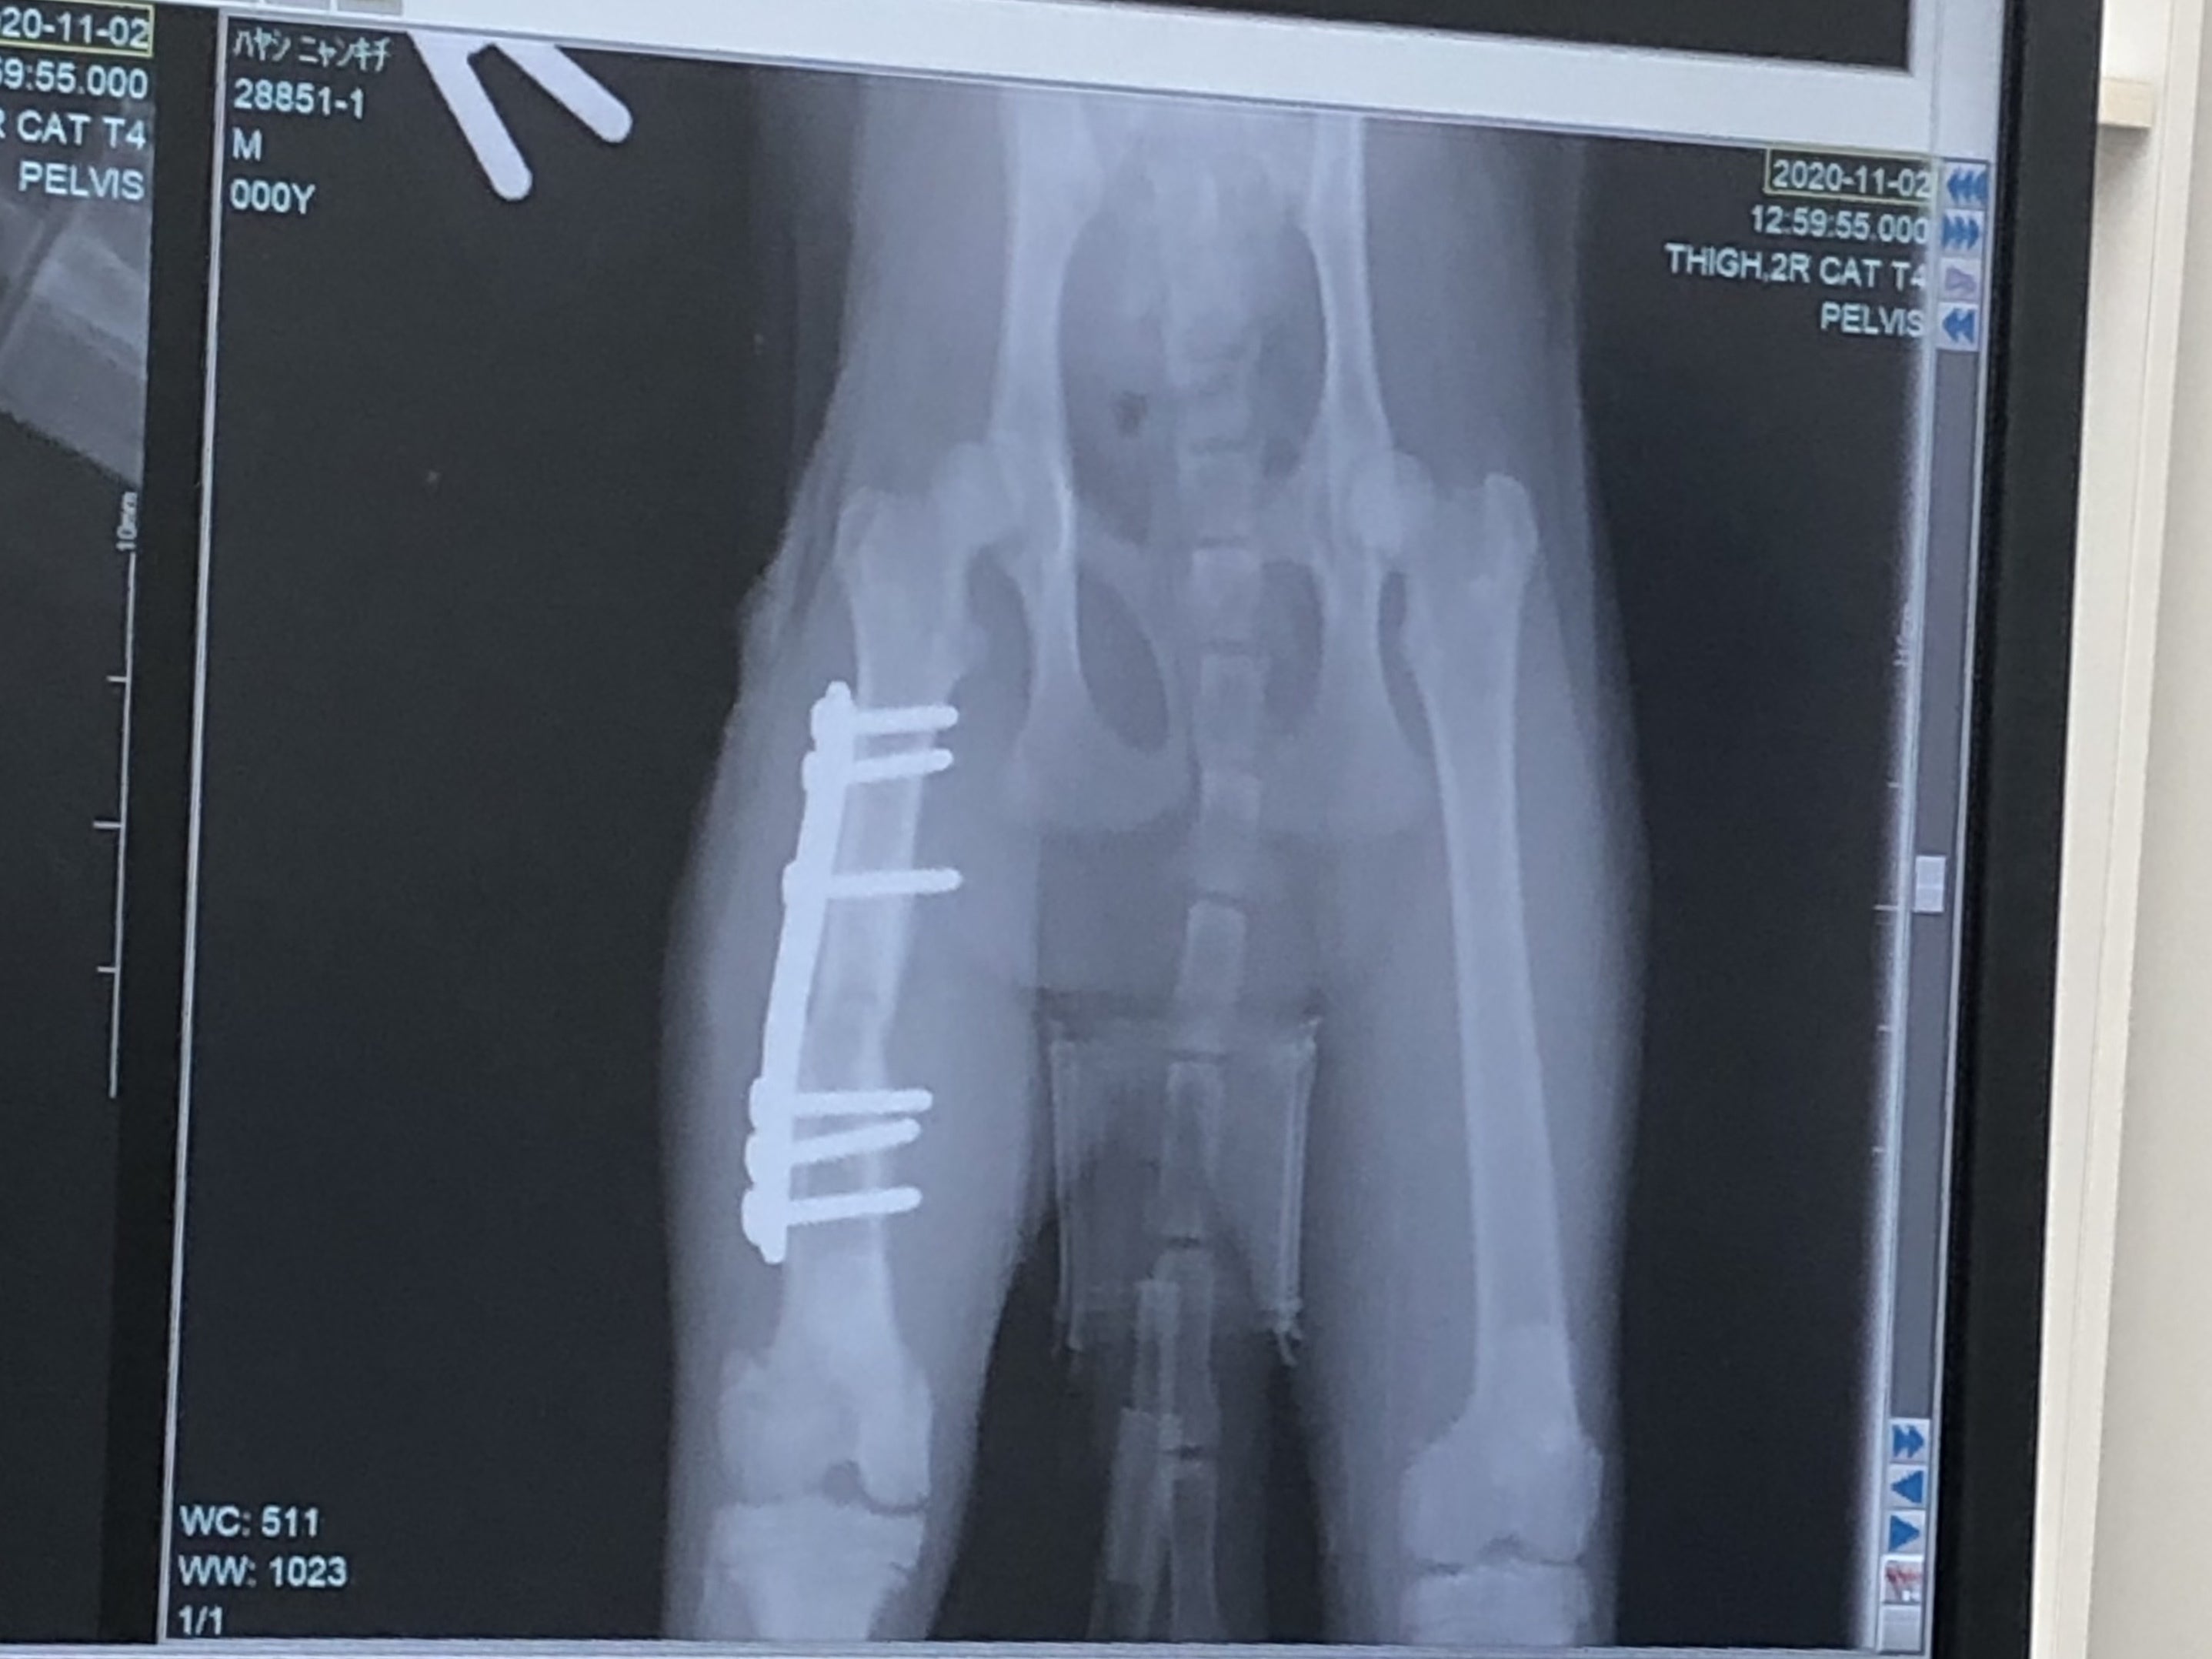

「右後ろ大腿骨(付根)」は肉を剥がして奥まで入った骨を戻し、固定の金具をつけます。

次に金具を入れて固定した画像。The 骨折画像と比べると、本当に綺麗に固定されていました。でもまあ、よくこんな折れた状態で店まで、歩いてきたなと。